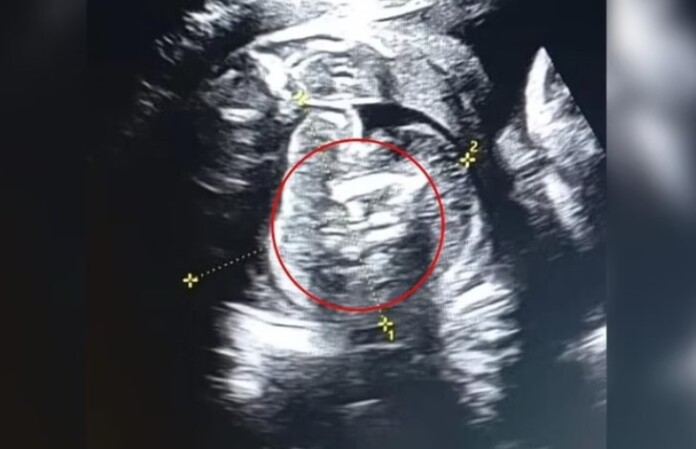

Uma mulher indiana de 32 anos foi surpreendida na 35ª semana de gestação ao descobrir que seu bebê carregava dois fetos dentro do abdômen. O caso raríssimo, conhecido como “feto dentro de feto”, foi relatado por médicos do Buldhana Women’s Hospital.

O parto aconteceu em 1º de fevereiro. Após o nascimento, os médicos removeram os dois fetos do abdômen do bebê. Eles haviam parado de crescer durante a gestação e não possuíam órgãos vitais completamente formados. Tanto a mãe quanto a criança passam bem.